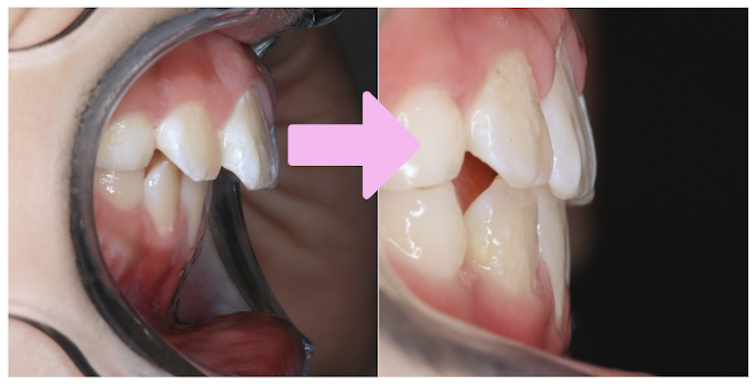

噛み合わせの深さ(オーバーバイト)は、スタートから4ヶ月で5mmから2mmの数値改善が見られました!

以降も取り組みを頑張ることで理想的な数値を維持できており、開始から1年2ヶ月経った現在の写真を見ても、噛み合わせが浅くなってきていることが分かりますね。

前歯の出具合(オーバージェット)は、9ヶ月で6mmから2mmの数値改善が見られました!

現在は1.5mmまで数値改善されています。